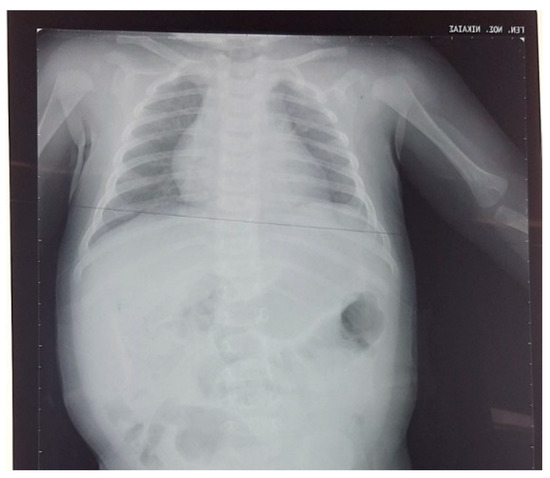

At 8 days of life, the mother was referred to our neonatal intensive care unit (NICU) for further investigation as vomiting persisted. Clinical examination revealed a fixed right clavicle fracture and brachial plexus paresis, while the vital signs were normal, and there were no signs of respiratory difficulty. The laboratory assessment showed: hemoglobin 14.4 gm%, hematocrit 40.3%, total leucocyte count 12,890 k/μL, polymorphs 21.3%, monocytes 0.5%, lymphocytes 54.8%, platelets 449.000 k/μL, sodium/potassium 139/5 mmol/l, calcium 10.2 mg/dl, total bilirubin 6.3 mg/dl, C-reactive protein negative, and arterial blood gases were normal. Both chest and abdominal X-rays showed elevation of the left hemidiaphragm with the possible existence of a hernia sac and the presence of intestinal helices in the left hemithorax (Figure 2).

Figure 2. Chest radiograph at admission showing elevation of the left hemidiaphragm (red arrow) and right clavicle fracture (yellow arrow).